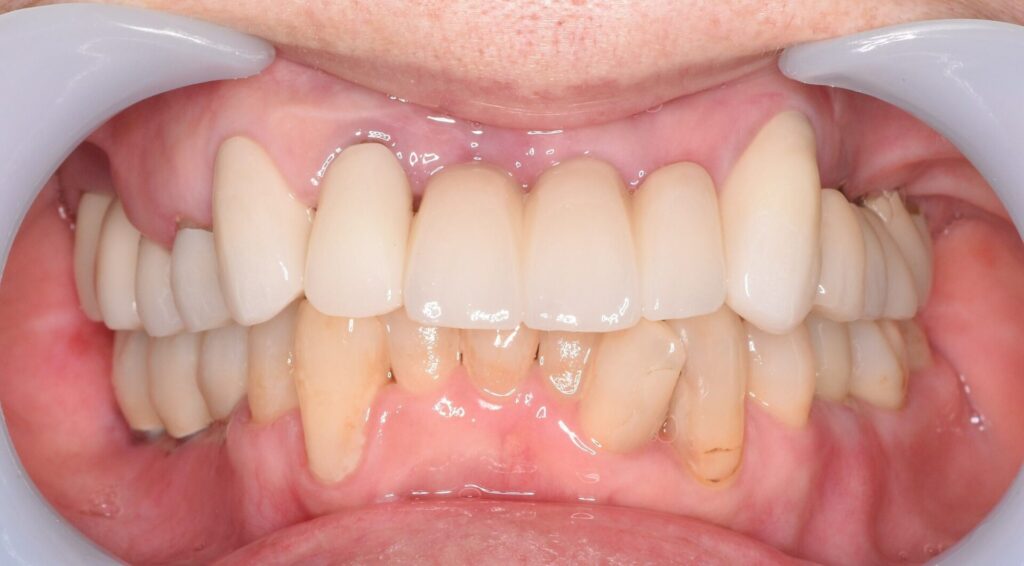

After

| 治療方法 | ・左上の奥歯と前歯は残せなかったため抜歯をしインプラント手術を行い、治癒を待つ間に仮の歯を入れて噛める状態にしてから右下の奥歯のインプラント手術を行いました。 その後、インプラントと骨がしっかりと結合したことを確認し、ジルコニアボンドを被せる治療を行っています。 ・右上は根がしっかりしていたので、根の治療からやり直し、ジルコニアボンドのブリッジを入れました。 |

| 費用 | ◎インプラント7本埋入 1次オペ代:1,925,000円 2次オペ代:231,000円 ステント(インプラント埋入用ガイド)77,000円 上部構造:1,155,000円 右上ジルコニアボンドブリッジ代693,000円 |